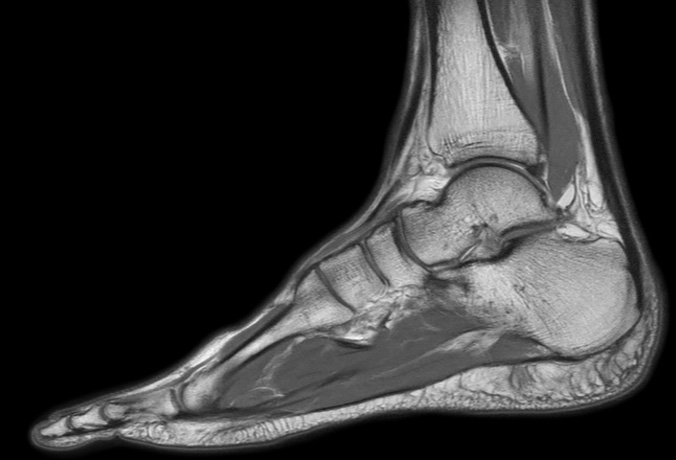

Sagittal PDw mDIXON TSE  (water only)